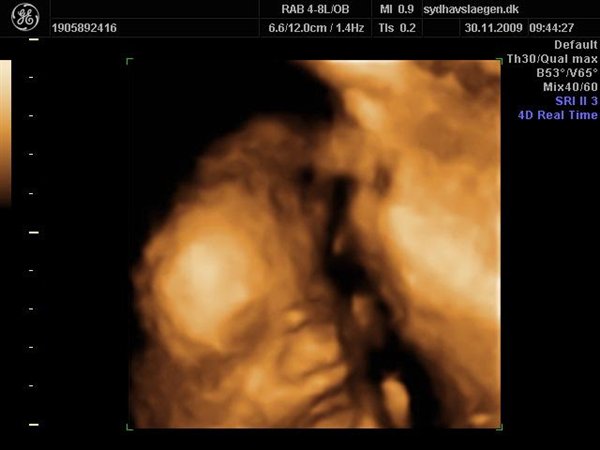

Da jeg snakkede med hende i dag sagde hun at fra uge 27 til og med uge 31 var det bedste tidspunkt at få det gjort....

Vi skal give 1400 kr for 45 minutters total gennem scanning, hvor hun fortæller, undersøger babyen fra top til tå, laver vægtskøn også får vi billeder og dvd med hjem.... Og ja det er da mange penge, men min forlovede har haft en masse vikar timer den her mdr, også sagde han at han syntes vi skulle bruge de penge på noget vi normalt ikke ville have gjort. Han sagde egentlig at jeg kunne gå ud og shoppe for dem, men jeg har termin om ti uger, så gider ærlig talt ikke bruge penge på nyt graviditets tøj, så hellere det her som vi egentlig havde valgt fra pga prisen, men som vi begge to rigtig gerne vil....